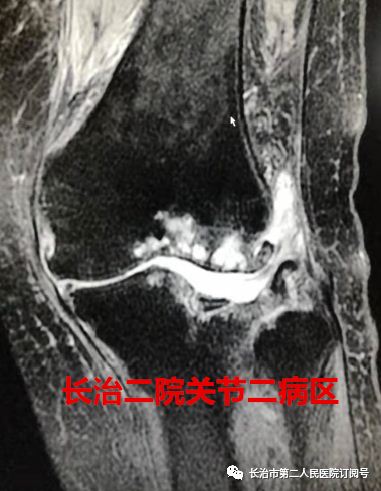

走路 在常人来看 是件多么轻松的事情 可对于李老太来说 近日,长治二院骨科关节二病区来了一位严重类风湿性关节炎患者,疾病困扰了她13年,日常行走已经很困难了。 长治二院骨科关节二病区 雷晓宇医师团队妙手回春 完美实施双膝关节置换术 随即轻松行走! 对李老太来说 走路成为了一种享受 今年69岁的李老太在13年前双膝先后出现疼痛无力的症状,但随着年龄的增长病情逐年加重,双腿关节等处都严重变形。双膝并拢时成“顺风腿”畸形,行走也变得相当困难,行各种保守治疗方案效果差,双膝疼痛行走受限,严重影响了日常生活。 图为:术前MRI及CT 图为:术后X片 据李老太的主管医生朱彦伟副主任医师介绍“重度外翻性膝行膝关节置换,由于其软组织不平衡及存在严重的骨缺损,手术难度极高,对于关节外科医师而言,绝对是充满挑战性事件! 入院后,骨科关节二病区雷晓宇医师团队术前进行仔细的手术规划,充分的术前准备,为李老太制定个性化治疗方案,对存在不同严重畸形的双膝分别行人工膝关节表面置换术。术后第二天就可以在助行器的保护下下床行走。经过精心的康复治疗,目前李老太的行走步态正常,生活质量明显提高。科室医护人员对李老太住院期间的精心治疗和护理,更是让老人及家属感受到了长治二院医护团队的专业素养和暖心服务。 对于像李老太这样的类风湿性关节炎患者,长治二院骨科关节二病区雷晓宇主任特别提醒:一旦出现疼痛、关节畸形、保守治疗无效后,应尽早行膝关节置换。 朱彦伟 关节二病区副主任医师 朱彦伟医师:周四全天门诊 电话:158 3551 0903 ■ 直通大医院丨9月18日长治二院关节外科一病区主任张鹏为您讲解《股骨头坏死的预防与诊治》 ■ 皮肤病患者的福音——又一“名医工作室”落户长治二院!!! ■ 长治二院特邀北京大学第一医院皮肤科教授陈喜雪来院指导讲学 供 稿丨朱彦伟 视 频 | 朱彦伟 编 辑丨张静晗 审 核丨雷 赫